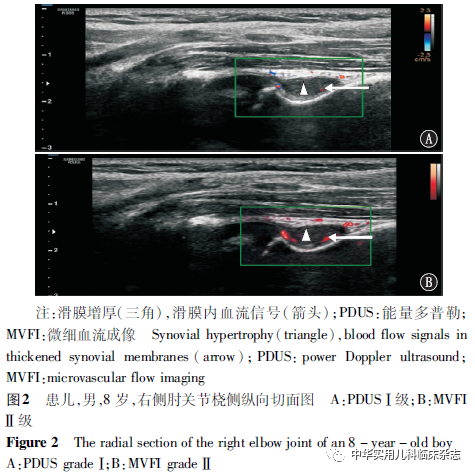

结果2.1 HAA患儿超声检查病变情况 共254个关节超声检查发现异常改变,其中肘关节、膝关节及踝关节累及数分别为30个、162个及62个。受累关节中滑膜增厚188个、关节腔积液146个、纤维隔膜66个、软骨改变63个、含铁血黄素沉积45个、骨侵蚀25个、骨赘形成15个及骨重建8个。2.2 HAA患儿受累关节滑膜增厚分级情况 188个滑膜增厚的关节中,膝关节128个,踝关节36个,肘关节24个。对受累膝关节、踝关节及肘关节进行滑膜增厚程度分级,均以 Ⅱ 级滑膜增生的关节居多(表1)。2.3 PDUS与MVFI增厚滑膜血流显示情况 HAA患儿188个增厚滑膜关节中PDUS血流显示率为52.66%(99/188个),MVFI血流显示率为70.21%(132/188个)。两成像方式增厚滑膜血流显示间差异有统计学意义(χ2=12.225,P<0.05)。2.4 PDUS与MVFI增厚滑膜血流分级情况 HAA患儿增厚滑膜内MVFI分级0级、Ⅰ 级关节数目均少于PDUS,但 Ⅱ 级、Ⅲ 级关节数目均多于PDUS。增厚滑膜内MVFI与PDUS血流分级差异有统计学意义(P<0.05)(表2,图1~3)。MVFI较PDUS可更敏感地显示增厚滑膜血流状况。

讨论血友病是一种X染色体连锁隐性遗传性出血性疾病,分为A型及B型血友病,男性发病,女性多为携带者,病患常表现为轻微刺激或自发的关节、内脏及深部组织出血,以关节出血最为常见[1]。反复的关节内出血可刺激关节内滑膜增生及滑膜内新生血管生成,早期关节改变类似于类风湿关节炎的炎性改变,随着病情发展,病变累及软骨与骨,发展为类似骨性关节炎的HA[2]。HA严重影响患者生活质量,是其致残的主要原因[1]。早期对关节进行定期监测、评估关节状况,有助于及时调整治疗方案,对维持关节功能具有重要意义。MRI、超声及X线是HA影像学评估的主要方式。X线检查虽可发现晚期关节病变,但对关节早期软组织改变的识别价值有限[11]。MRI具有较高的组织分辨率,不仅能显示关节不同时期的出血改变,滑膜增厚及含铁血黄素沉积状况,还能够发现关节面的微小病灶,是目前检测HA的金标准,但存在检查时间长、花费高,儿童需镇静,不利于连续随访等不足[12]。多项研究[4,12-14]均表明超声在HA评估方面与MRI显著相关,检出滑膜增厚及软骨改变方面二者间差异不明显。超声作为一种安全、快捷、有效的检查方法,在检查HA中具备一定的优势。超声二维灰阶模式下对关节滑膜及关节周围结构(包括肌腱、韧带及肌肉)均可进行详细、动态的评估[4]。MRI平扫无法显示滑膜炎的活动性,但超声PDUS模式对增生滑膜血流信号敏感,可反映滑膜血流状况及炎症的活动性,与动态增强MRI显著相关,是评估HA滑膜炎的一种简单易行的方法[14-15]。本研究对82例HAA患儿的双肘、双膝及双踝492个关节超声检查发现,共254个(52.63%)关节受累,以膝关节(32.93%)受累最为多见,其次是踝关节及肘关节,与既往研究相一致[13]。受累关节常见超声征象的检出率依次为滑膜增厚(74.02%)、关节腔积液(57.48%)、纤维隔膜形成(25.98%)、软骨改变(24.80%)、含铁血黄素沉积(17.72%)、骨侵蚀(9.84%)、骨赘形成(5.91%)、骨重建(3.15%),与相关研究[13,16]对HA异常超声征象的检出率略有不同,考虑与研究对象的年龄、受检人群病变严重程度及被检关节有关。本研究中,统计增厚滑膜关节发现,膝关节所占比例最高(68.08%),其次为踝关节(19.15%)及肘关节(12.77%),对膝关节、踝关节及肘关节增厚滑膜进行分级可知均以 Ⅱ 级滑膜增生多见。反复的关节内出血刺激关节腔内滑膜增殖及新生血管的形成,炎症增生的滑膜及脆弱的新生血管更易受伤及出血,形成恶性循环,炎症滑膜的治疗在打破HA“出血-滑膜炎-再出血”恶性循环中尤为重要[3]。高频超声可检测评估关节腔内增生滑膜,PDUS模式能够对新生血管进行显示,评估关节的炎症活动性[17]。MVFI作为新的一种微血流显像模式,具备更高的空间分辨率及帧频成像、操作简单、可重复等优势,较临床常用的PDUS可更敏感地检测极低速血流信号,更准确地评估滑膜炎[5]。本研究对增厚滑膜PDUS与MVFI血流显示率比较发现,MVFI血流显示率约为PDUS的1.3倍,MVFI对增厚滑膜血流显示方面更具有优势。比较增厚滑膜PDUS与MVFI血流分级,PDUS模式下0级、Ⅰ 级多见,而MVFI模式下 Ⅱ 级、Ⅲ 级血流多见,对于同组患儿,MVFI可上调PDUS血流分级级别。本研究不足之处为单中心研究,且为初步研究,缺乏与MRI的比对,亦未探讨不同严重程度血友病间及不同出血次数间MVFI的差异,需要进一步增加样本量及评估指标来探究。综上所述,MVFI技术具备操作简单、安全可重复、对增厚滑膜内低速血流较为敏感等优势,能更好地检测及评估儿童HAA增厚滑膜内血流灌注及分级情况,高频超声联合MVFI技术在评估HAA中具有一定的应用价值。